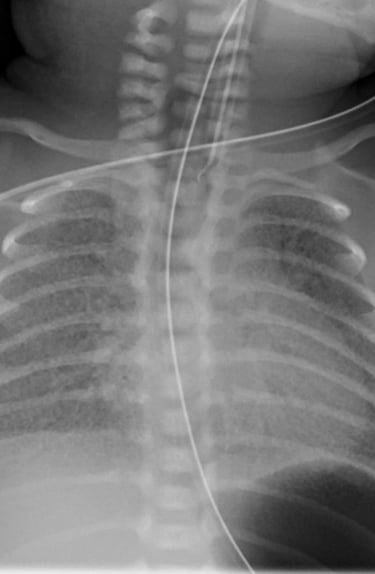

Berat badan lahir bayi 4.500 gram, dan mengalami gangguan napas beberapa saat setelah lahir. dengan skor Downe 5, yaitu ada takipne, merintih dan napas cuping hidung, saturasi oksigen 80%.

Gambaran rontgen paru sebagaimana terlampir.